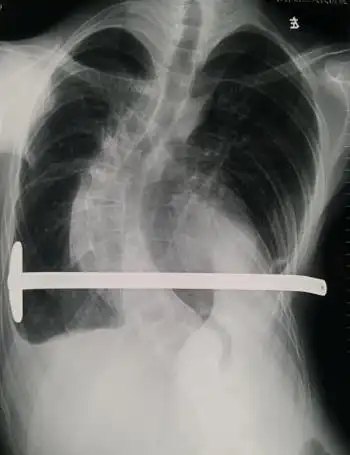

ct提示胸廓复合型畸形,胸骨下端凹陷,左侧前胸壁前突,心脏位于左侧